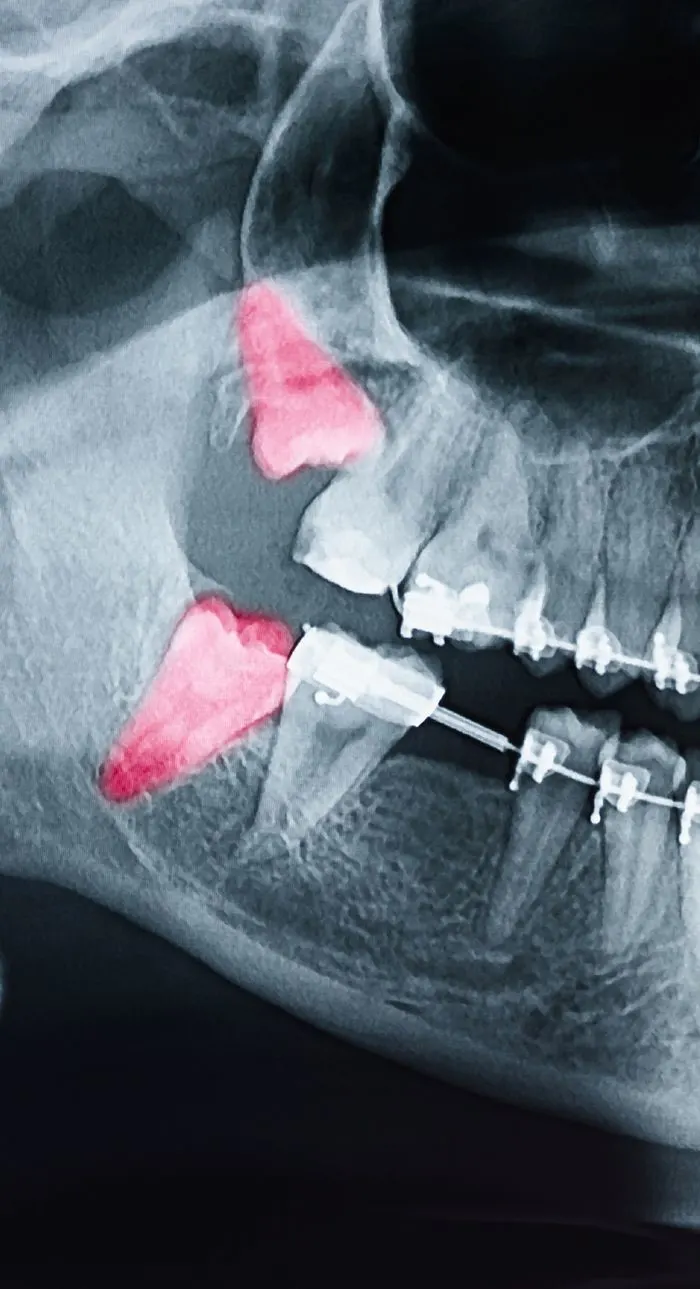

During your consultation, we’ll take digital x-rays to assess the condition of your tooth and the surrounding bone. We’ll explain whether extraction is truly necessary and walk you through any alternatives. If you’re moving forward, we’ll review the number of teeth to be removed, aftercare expectations, and any follow-up recommendations for tooth replacement. We’ll answer every question you have so you feel fully informed and know what to expect.

Tooth extractions are typically recommended when a tooth is beyond repair due to severe decay, advanced gum disease, trauma, or infection. Sometimes, a tooth may need to be removed to make room for orthodontic treatment or to prepare for a dental implant or denture.

Wisdom teeth are often extracted if they’re impacted, causing pain, or crowding surrounding teeth. Your dentist will always explore all options before recommending removal, but sometimes extraction is the best way to protect your long-term oral health.